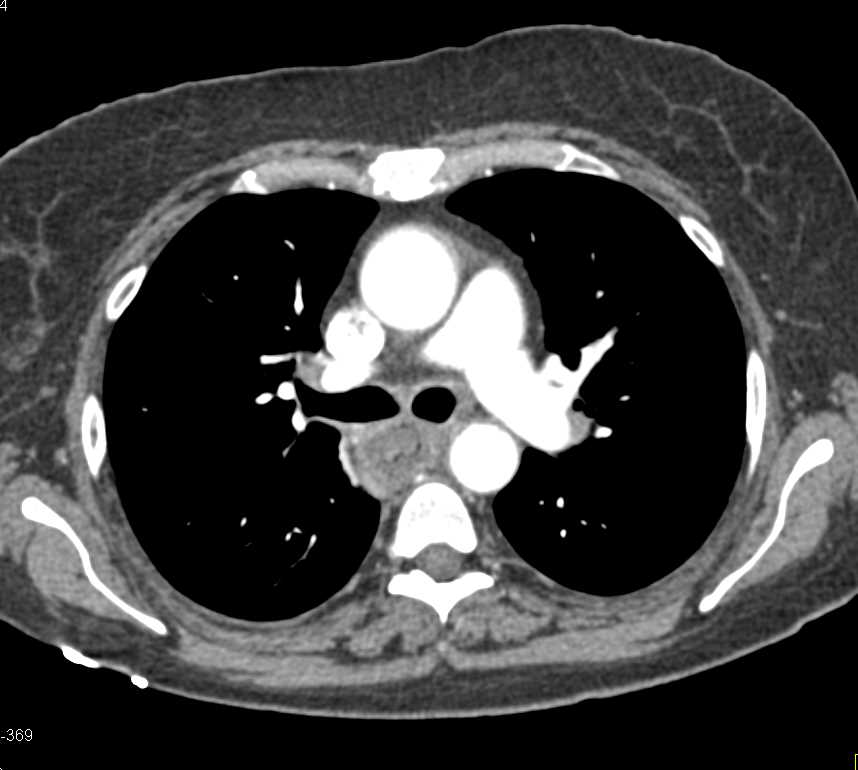

Severe Esophagitis in Oncology Patient